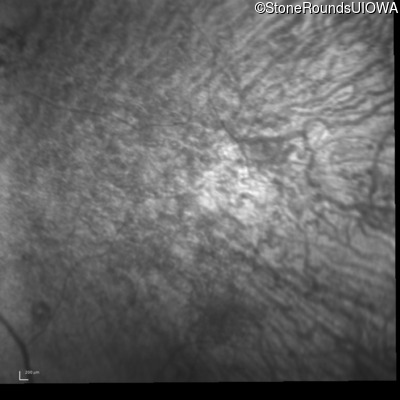

This 41 year old man first came to medical attention at age 18 months when exotropia and amblyopia of his right eye were discovered. At age 11 vitreous strands and retinal vascular sheathing were seen. He has had poor night vision and constricted visual fields since his late teens. Later, at age 44 a traction retinal detachment was noted in his left eye and was treated with a scleral buckle.

Age at visit: 41 years